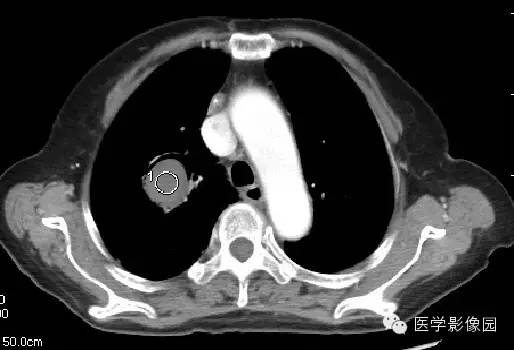

影像表现为肺内空洞病灶内有圆形软组织密度影,改变体位后曲菌球位置可变动,曲菌球与洞壁见出现一新月形间隙,称为“新月征”。